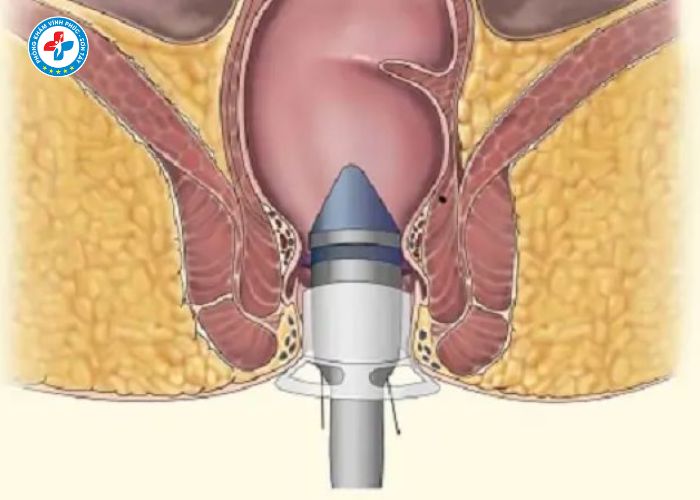

Quy trình tiêm trĩ tại Sơn Tây diễn ra như thế nào?

Quy trình tiêm trĩ thường được thực hiện theo các bước:

1. Thăm khám ban đầu

- Bác sĩ kiểm tra mức độ trĩ

- Xác định vị trí búi trĩ

2. Vệ sinh và gây tê

- Làm sạch vùng hậu môn

- Gây tê nhẹ để giảm khó chịu

3. Tiêm xơ búi trĩ

- Tiêm thuốc vào chân búi trĩ

- Thuốc làm co mạch và xơ hóa búi trĩ

4. Theo dõi sau tiêm

- Nghỉ ngơi ngắn tại cơ sở y tế

- Hướng dẫn chăm sóc tại nhà

👉 Toàn bộ quy trình chỉ mất khoảng 15–30 phút.